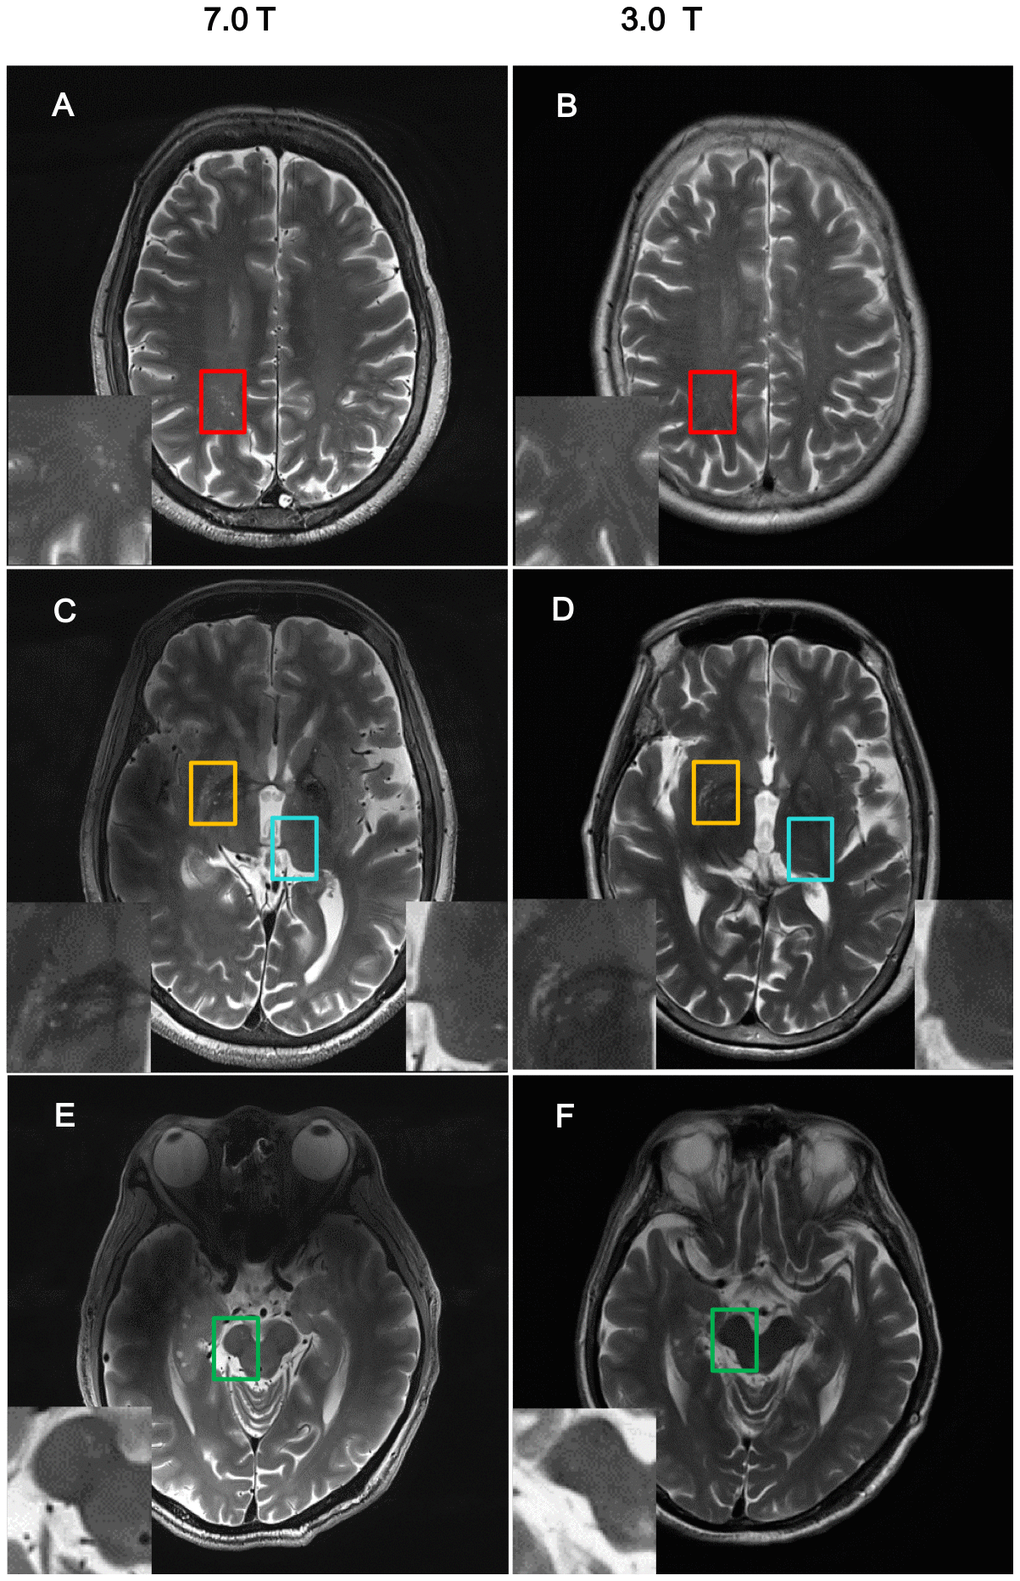

With 7T MRI, the resolution of the images was high enough to allow analysis of nPVS burden (Figure 1). NPVS number and volume calculation of PD subgroups and HCs groups were performed (Table 2). Test-retest reliability using the two-way mixed model for absolute agreement over a one-month interval reached 0.79 and 0.80 for nPVSs number and volume of BG region, 0.72 and 0.74 of thalamic region, 0.89 and 0.93 for the CSO region, and 0.77 and 0.83 of the midbrain, respectively.

Figure 1. Comparison of imaging resolution between 7T and 3T MRI for nPVS. Example of comparisons of resolution of nPVSs on T2 weighted images acquired by 7.0T MRI vs 3.0T MRI on the same study participant. (A, B) Indicate centrum semiovale with red square; (C, D) indicate yellow squares for basal ganglia and blue squares for thalamus; (E, F) is midbrain with green squares. nPVS, normal-sized perivascular space.

MR images were acquired with a 7T Magnatom research system (Siemens Healthcare, Erlangen, Germany) with a T2-weighted turbo spin echo (TSE) sequence (voxel size: 0.5 × 0.5 × 2.4 mm3, TR = 7000 ms, and TE = 66 ms), and two rapid gradient echoes (MP2RAGE) sequence (voxel size: 0.7 × 0.7 × 0.7 mm3, TR = 5000 ms, TI1/TI2 = 900/2750ms, TE = 2.3 ms, α1/α2 = 5°/3°). The nPVS burden, nPVS number and volume, were calculated with the axial T2-weighted TSE images via ITK-SNAP Software version 3.8 (http://www.itksnap.org/) by a neurologist blinded to the participant’s diagnosis and clinical features. For nPVS volume assessment, the border of each nPVS in the chosen slice was drawn manually. The nPVS volumes within the border were calculated automatically by the toolbox. The number of nPVSs were counted in the BG, thalamus, midbrain and CSO regions (Figure 1). For BG, thalamus, and CSO, nPVSs were assessed on the slice unilaterally with the highest number for left or right side, followed by the sum of both sides. We then assess a single slice with the highest total nPVS count. For midbrain, given it is a small structure, nPVSs were counted within all slices showing midbrain. A 4-point visual rating scale (0 = no PVSs, 1 = PVSs < 10, 2 = 11-20 PVSs, 3 = 21-40 PVSs, 4 = PVSs > 40) were used to grade the severity of PVS [66]. PVSs severity was then assessed using a semi-quantitative scale (none/mild = 0/1, moderate = 2, frequent/severe = 3/4) [43]. All patients were included for test-retest reliability testing. The WMH burden for all participants was assessed by using a semi-quantitative rating scale [67].